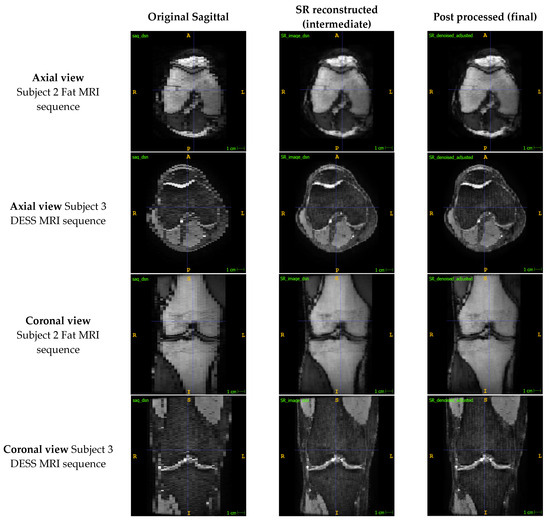

Appendix A.1. Presenting the Comparison between SR Images Reconstructed with Two Planes vs. Three Planes